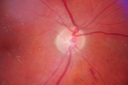

Nonproliferative Diabetic Retinopathy2273 views65-year old female with diabetes. Has had cataract surgery in the left eye with VA 20/25. She has had laser in the past. Fundus examination shows microaneurysms with retinal hemorrahages and exudates in the left eye. Feb 04, 2013

Nonproliferative Diabetic Retinopathy2764 views65-year old female with diabetes. Has had cataract surgery in the left eye with VA 20/25. She has had laser in the past. Fundus examination shows microaneurysms with retinal hemorrahages and exudates in the left eye. Feb 04, 2013

Nonproliferative Diabetic Retinopathy4359 views65-year old female with diabetes. Has had cataract surgery in the left eye with VA 20/25. She has had laser in the past. Fundus examination shows microaneurysms with retinal hemorrahages and exudates in the left eye. Feb 04, 2013

Nonproliferative Diabetic Retinopathy5551 views65-year old female with diabetes. Has had cataract surgery in the left eye with VA 20/25. She has had laser in the past. Fundus examination shows microaneurysms with retinal hemorrahages and exudates in the left eye. Feb 04, 2013

Nonproliferative Diabetic Retinopathy5728 views65-year old female with diabetes. Has had cataract surgery in the left eye with VA 20/25. She has had laser in the past. Fundus examination shows microaneurysms with retinal hemorrahages and exudates in the left eye. Feb 04, 2013

Nonproliferative Diabetic Retinopathy6602 views65-year old female with diabetes. Has had cataract surgery in the left eye with VA 20/25. She has had laser in the past. Fundus examination shows microaneurysms with retinal hemorrahages and exudates in the left eye. Feb 04, 2013

Nonproliferative Diabetic Retinopathy8138 views65-year old female with diabetes. Has had cataract surgery in the left eye with VA 20/25. She has had laser in the past. Fundus examination shows microaneurysms with retinal hemorrahages and exudates in the left eye. Feb 04, 2013

Nonproliferative Diabetic Retinopathy7481 views65-year old female with diabetes. Has had cataract surgery in the left eye with VA 20/25. She has had laser in the past. Fundus examination shows microaneurysms with retinal hemorrahages and exudates in the left eye. Feb 04, 2013